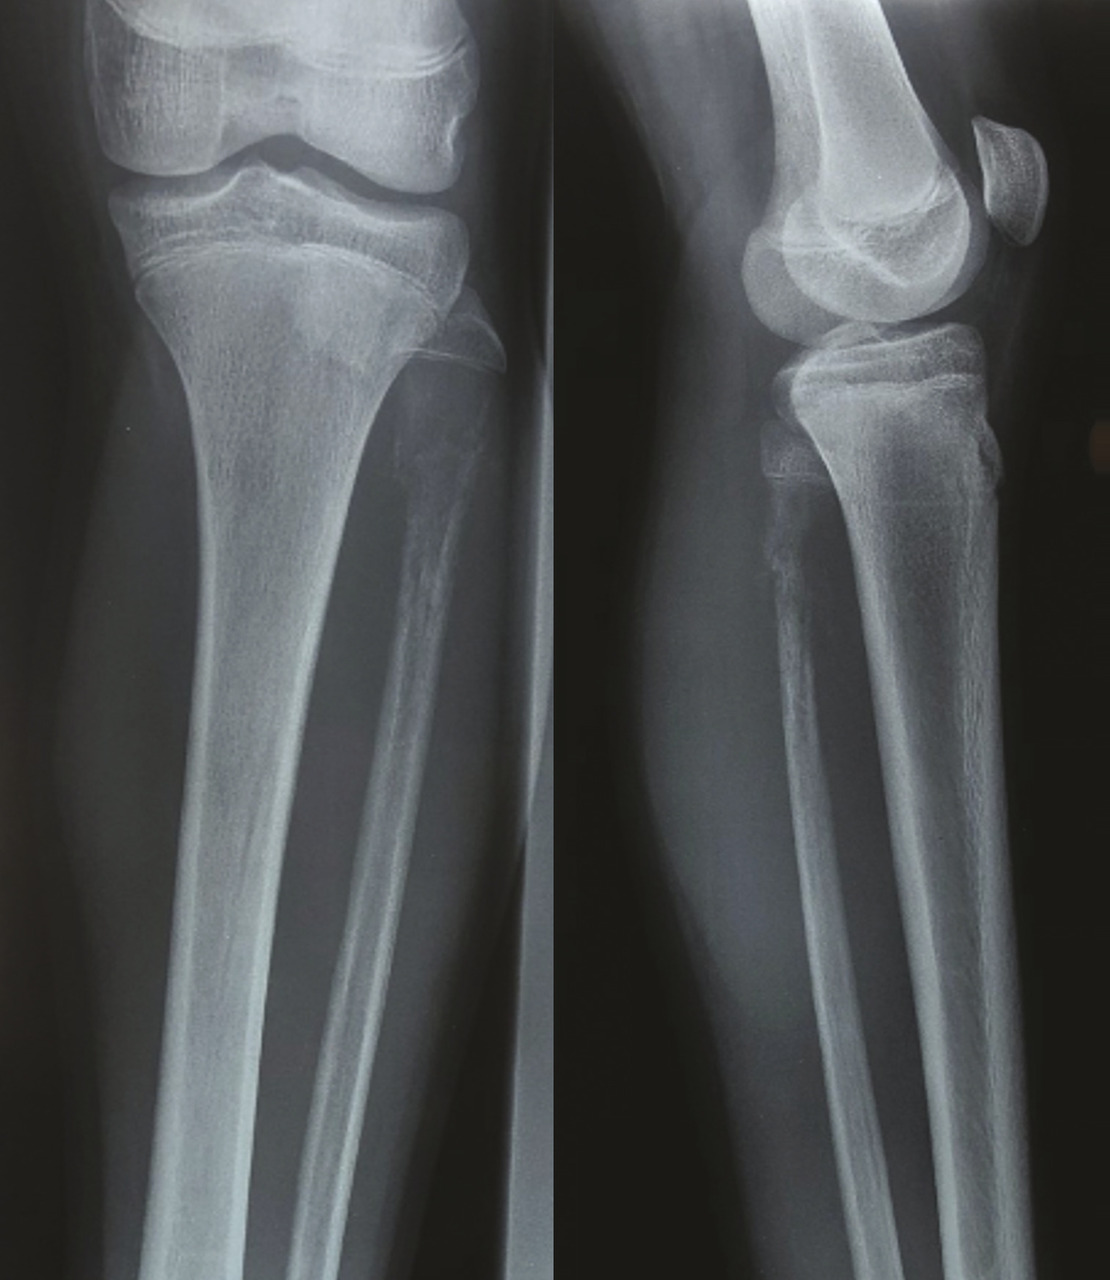

Un enfant de 14 ans, sans antécédents pathologiques particuliers, se plaint depuis un mois d’une douleur de la jambe gauche avec tuméfaction d’apparition progressive en externe. L’examen clinique trouve une masse fixe, de consistance dure et expansive dans la zone affectée sans autres signes pathologiques. Une radiographie montre un processus osseux centromédullaire expansif du tiers supérieur du péroné gauche avec une ostéolyse mitée et une réaction périostée en éperon de Codman (fig. 1 ). Une imagerie par résonance magnétique (IRM) décèle un processus tumoral osseux du tiers supérieur de la fibula centromédullaire métaphyso-diaphysaire se rehaussant de façon hétérogène après injection de produit de contraste ; ce processus envahit les parties molles adjacentes et respecte l’articulation tibio-fibulaire supérieure (fig. 2 ). Le diagnostic d’ostéosarcome est évoqué. Une biopsie est réalisée et l’étude anatomopathologique est en faveur d’un sarcome d’Ewing. Le scanner thoraco-abdomino-pelvien pratiqué ensuite pour rechercher d’éventuelles lésions métastatiques est normal. L’enfant a bénéficié d’une chimiothérapie néoadjuvante.